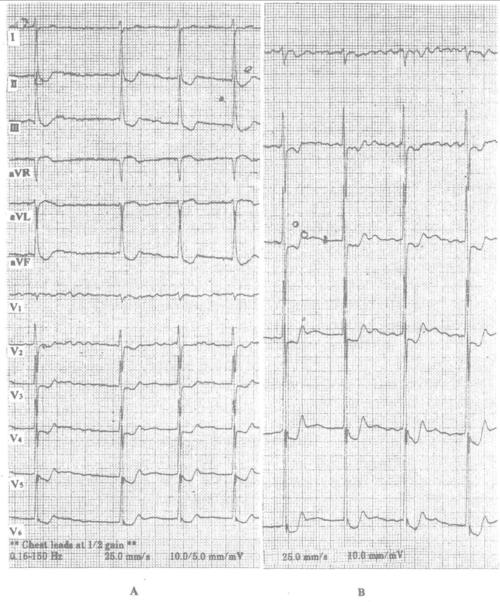

室性二联律心电图特点,室早二联律心电图特点

李女士的心电图提示为室早二联律

室早二联律心电图特点

室性早搏二联律心电图